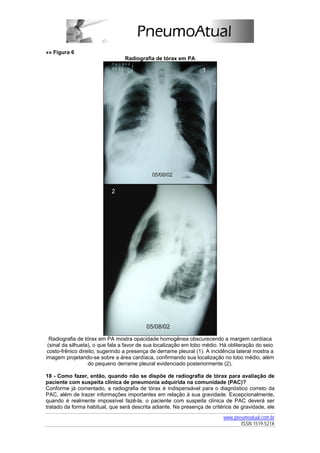

»» Figura 6

Radiografia de tórax em PA

Radiografia de tórax em PA mostra opacidade homogênea obscurecendo a margem cardíaca

(sinal da silhueta), o que fala a favor de sua localização em lobo médio. Há obliteração do seio

costo-frênico direito, sugerindo a presença de derrame pleural (1). A incidência lateral mostra a

imagem projetando-se sobre a área cardíaca, confirmando sua localização no lobo médio, além

do pequeno derrame pleural evidenciado posteriormente (2).